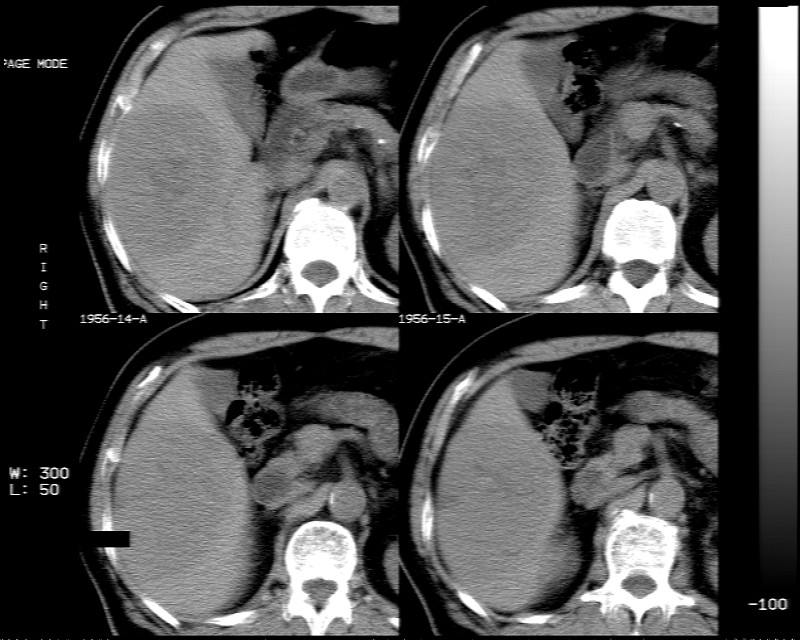

肝脏右叶块状低密度影,增强后动脉期明显强化,门脉期强化减低,延迟期病灶又成低密度。考虑肝细胞癌。我认为比较典型。

低密度肿块,动脉期明显强化,可见星状低强化区,门脉期强化向中心扩展,但病灶动脉期强化最明显,门脉期及平延迟期强化减低,结合病只考虑巨大局灶性结节增生,血管瘤不除外

肝右叶巨大占位性病变,平扫呈低密度改变,增强扫描动脉期病灶周围强化,门脉期强化未退出,延时期病灶周边强化与肝实质接近,病灶中心在各期均可见星状不强化区;首先考虑局灶性结节增生可能性大,其次为血管瘤。肝癌不能完全排外(不首先考虑肝癌是因为强化不支持快进快出特点)。

平扫示:肝右后叶下段内见类圆形略低密度占位病灶,边界尚清楚,最大径约为102×71mm,ct值31~41hu。

动态增强扫描示:动脉期病灶显著不均性强化,病灶强化密度高于肝实质;平衡期病灶呈等密度;延迟扫描病灶密度略低于肝实质;三期均见占位病灶内有裂隙状无强化影。肝内胆管无扩张,腹膜后未见肿大淋巴结。

拟诊:肝右后叶下段内占位性病变,考虑为肝结节样增生。

建议进一步检查(mri/或穿刺活检),不排外肝ca。